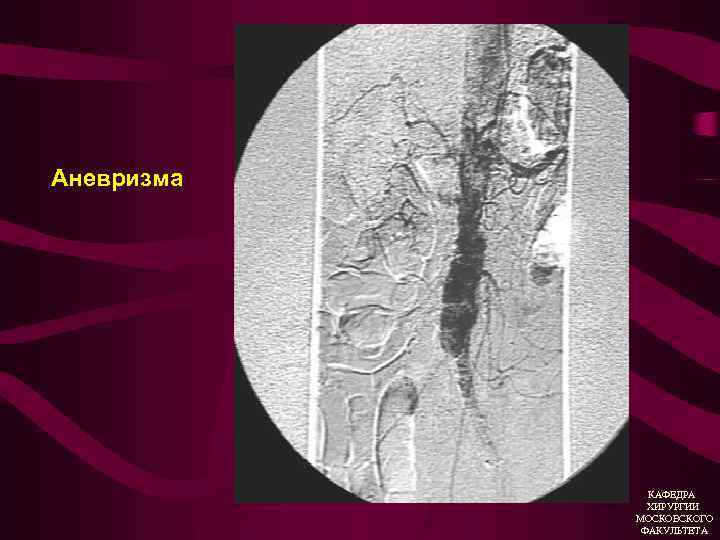

Дилятирующий атеросклероз Аневризмы 1. Истинная (расширение аорты или артерий в 2 раза и более без дефекта стенки 2. Ложная (паравазальная организованная пульсирующая гематома, вследствие дефекта в стенке аорты или артерии). КАФЕДРА ХИРУРГИИ МОСКОВСКОГО ФАКУЛЬТЕТА

Атеросклеротическая аневризма брюшной аорты • Боль (симптомная аневризма) • Атеросклеротический анамнез • Пульсирующее образование в брюшной полости, аускультативно систолический шум • УЗИ (дуплексное ангиосканирование) • Ангиография КАФЕДРА ХИРУРГИИ МОСКОВСКОГО ФАКУЛЬТЕТА

Аневризма КАФЕДРА ХИРУРГИИ МОСКОВСКОГО ФАКУЛЬТЕТА